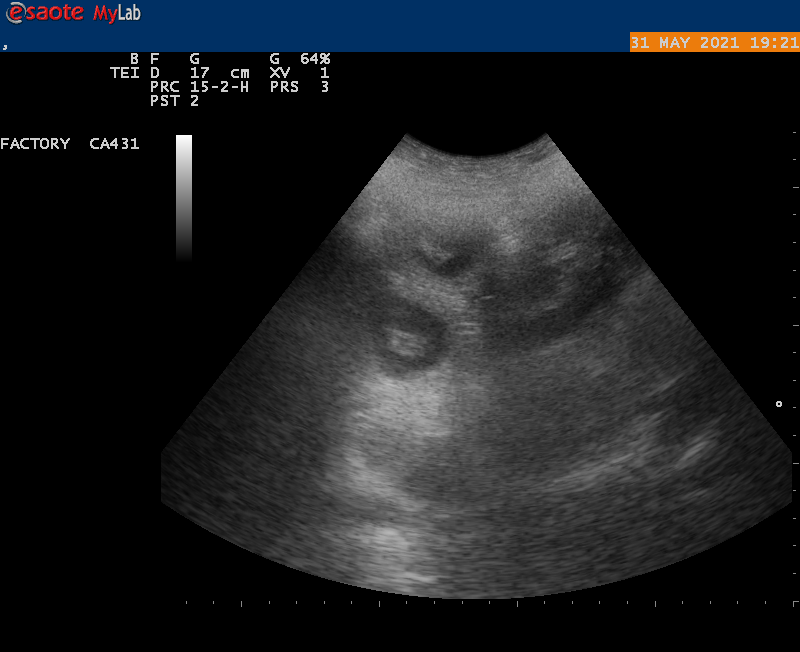

MAANDAG 31 MEI hebben we de echo laten maken, dit is de 30 ste dag van de dekking.

en YES onze Airen is drachtig je kon duidelijk verschillende vruchtblaasjes zien,

welke in de komende weken zullen uitgroeien tot newfy beertjes,